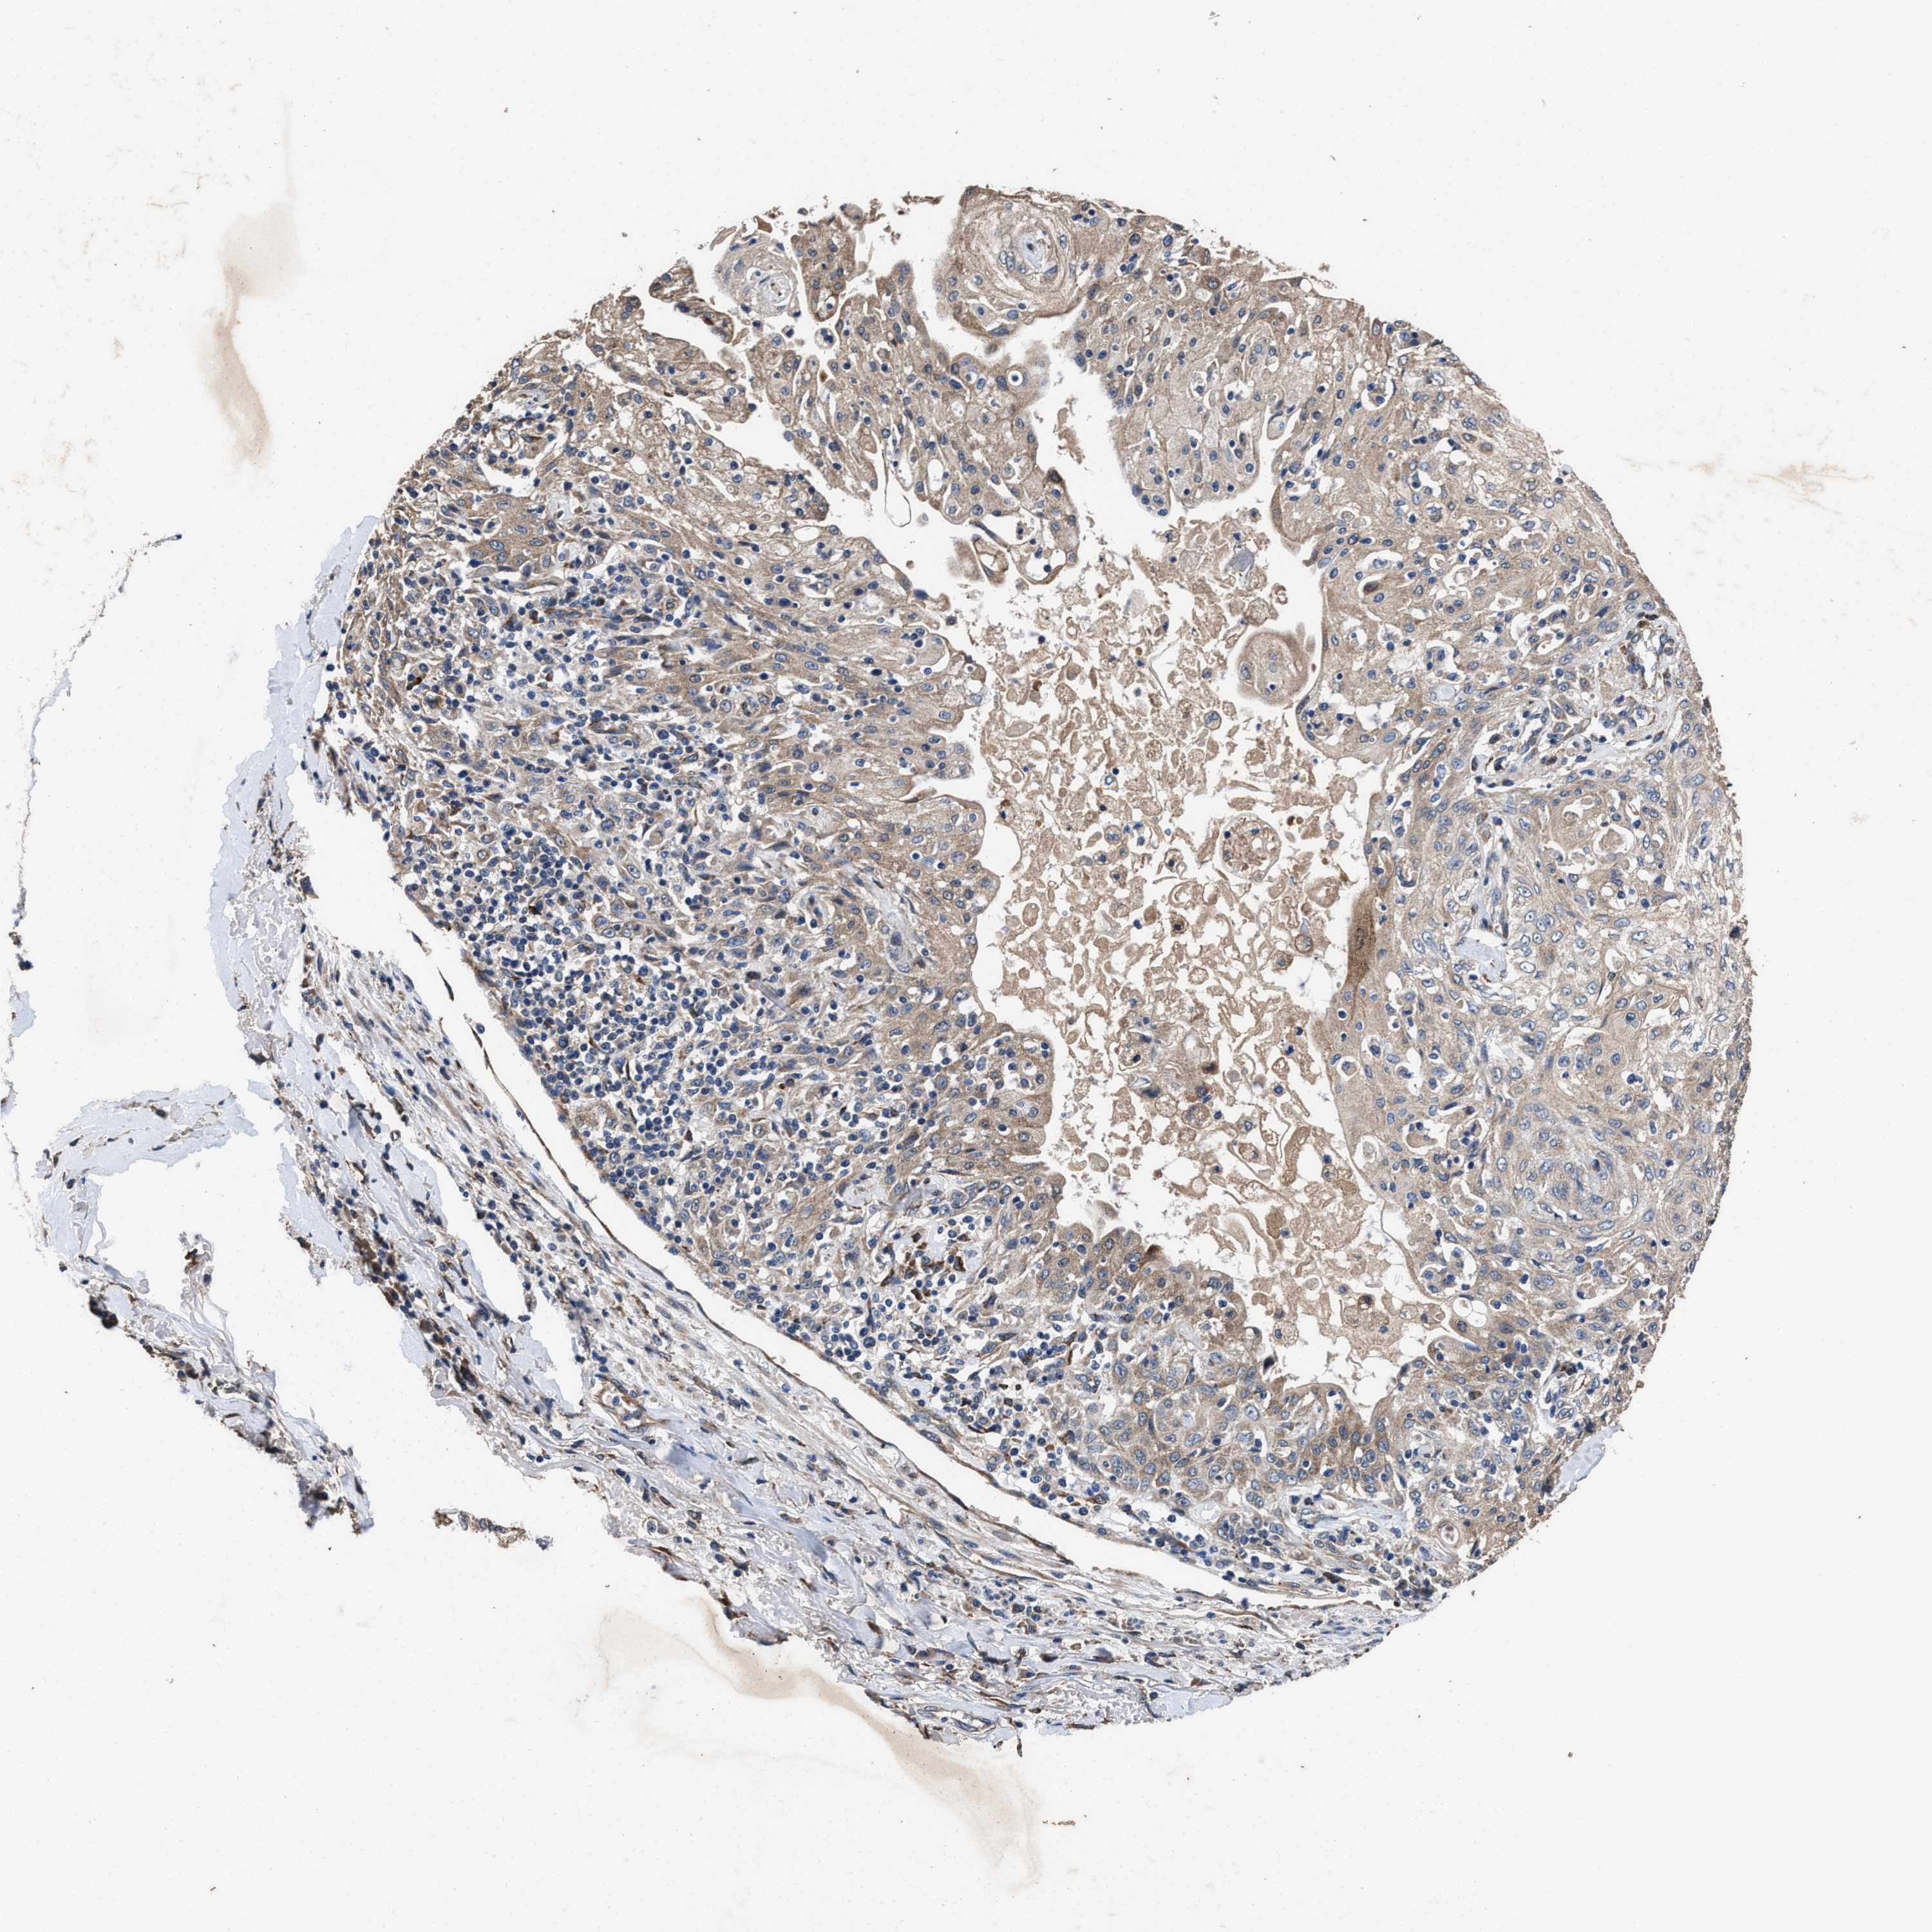

SKIN CANCER - Protein expressioni

A mouse-over function shows sample information and annotation data. Click on an image to view it in a full screen mode. Samples can be filtered based on level of antibody staining by selecting one or several of the following categories: high, medium, low and not detected. The assay and annotation is described here.

Antibody stainingi

Antibody staining in the annotated cell types in the current human tissue is reported as not detected, low, medium, or high, based on conventional immunohistochemistry profiling in selected tissues. This score is based on the combination of the staining intensity and fraction of stained cells.

Each image is clickable and will lead to virtual microscopy that enables deeper exploration of all samples and also displays staining intensity scores, fraction scores and subcellular localization as well as patient and tissue information for each sample.

Antibody HPA020378

Staining

High

Medium

Low

Not detected

Intensity

Strong

Moderate

Weak

Negative

Quantity

>75%

75%-25%

<25%

None

Location

Nuclear

Cytoplasmic/membranous

Cytoplasmic/membranous,nuclear

Squamous cell carcinoma, NOS

Squamous cell carcinoma, metastatic, NOS